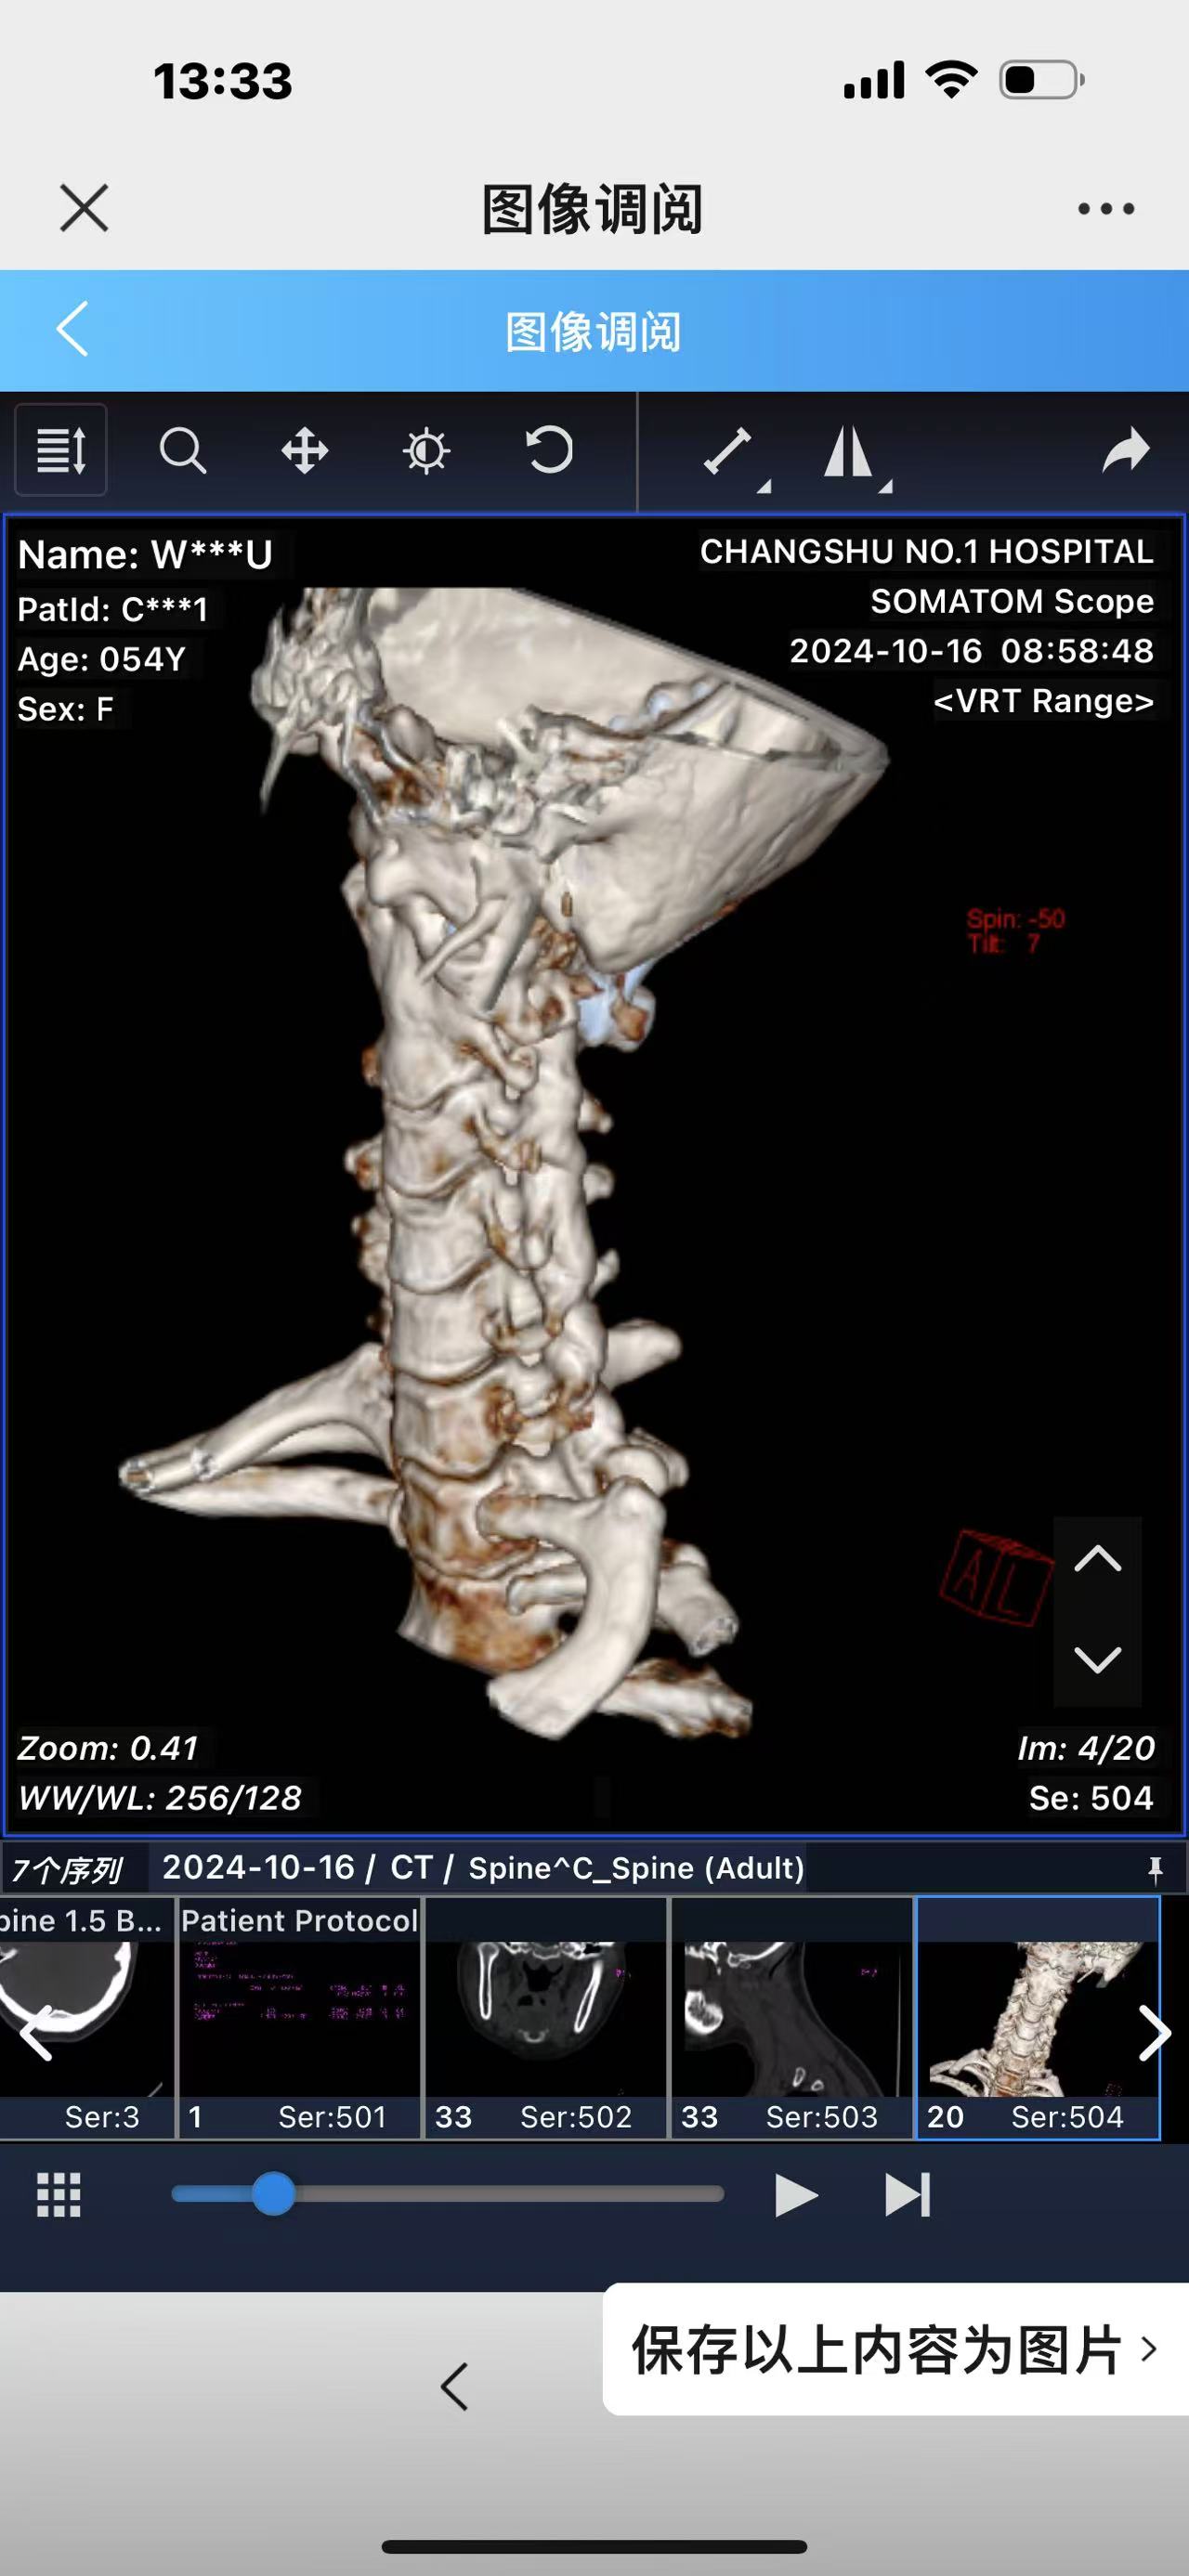

• 诊断:寰枢椎脱位,颅底凹陷

• 日期:2023.09

• 医院:北三医院

• 主刀:王超

• 术后影像:

• 2024.02.27,复查,对位良好,偶尔会肩甲骨酸,坐下就不酸。

• 2024.10.20,复查,对位良好,偶尔会肩甲骨酸,坐下就不酸。